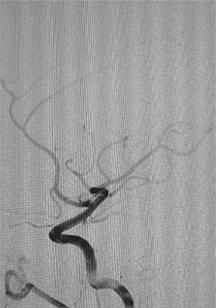

术后造影显示动脉瘤致密栓塞,各分支血管血流通畅。

术后双容积成像显示支架头端完全覆盖动脉瘤瘤颈,并且与Solitaire支架形成“Kissing”,“T型”形成。

术后:继续常规双抗100mg阿司匹林+75mg氯吡格雷管理3-6个月。

术后患者恢复良好出院,无明显神经系统症状。